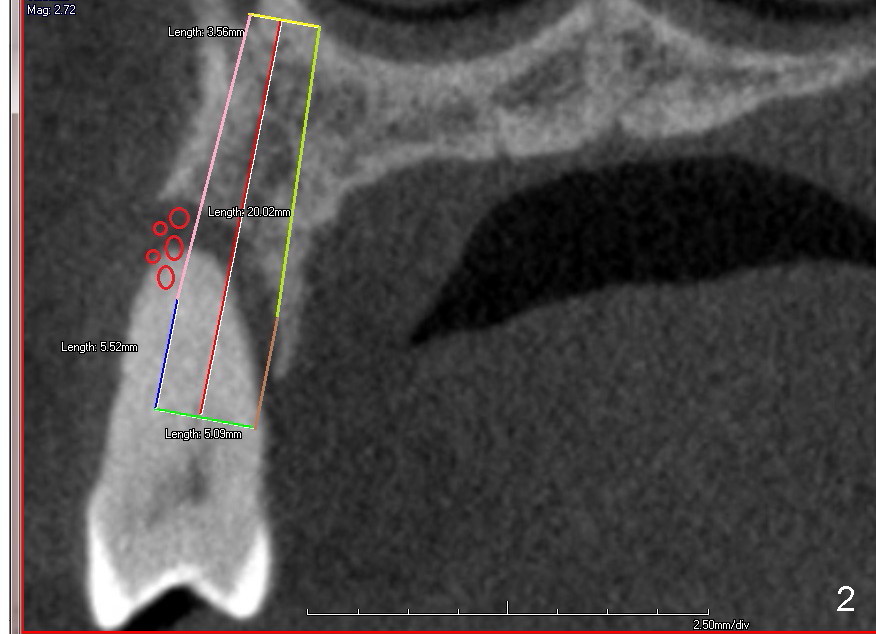

Immediate implant at the site of #13 is the last implant to be placed for full mouth reconstruction (Fig.1 CT sagittal section; 1 2 3 4 5 6 7 8). The sequence of the treatment is due to insurance benefit issues. In fact brackets for orthodontics were dislodged due to carelessness by the patient. He does not want to pursue this mode of treatment. Either prior to or after implant placement, bone graft will be placed distally (Fig.1: in large amount (red circles)) and buccally (Fig.2 (coronal section). If primary stability is acceptable, an immediate provisional is fabricated. He will be traveling abroad soon.

Fig.5 is an illustration showing the socket after extraction. The osteotomy is intentionally placed distally (Fig.6 arrow: pilot drill). In case the patient agrees to have ortho treatment, there will be space to correct the upper midline (7). If not, a molar crown will be fabricated. By the time a 4.5x20 mm tap is inserted (Fig.7 T), the mesial gap is visible (*). When a 6x20 mm implant is placed (Fig.8 I), bone graft is placed buccally (Fig.2, as planned) and mesially (Fig.8 red circles, as compared to Fig.1). The implant has to be as large and long as 6x20 mm to get primary stability (insertion torque 50/60 Ncm). The apex of the implant is close to the sinus floor (Fig.8 ^) or in fact the nasal floor (Fig.9 N). There appears bone growth in the mesial gap 3 months postop (Fig.10 *). There is no bone loss 2.5 years post cementation (Fig.11).

CT taken 4 years 9 months post cementation shows that the coronal portion of the buccal plate regenerates (Fig.12 between arrowheads, as compared to Fig.2,9). The density is ~1,000 Hounsfield Units, as compared to ~2,000 HU of the apical portion (Fig.13).